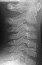

CASE HISTORY

Patient is a 4 year old male who developed the insidious onset of neck pain and stiffness 4 days prior to admission. Over the intervening period, the patient suffered from worsening of his symptoms which led to increasing irritability and difficulty sleeping. On the day of admission, he was seen by a local pediatrician for severe neck pain. It was observed that his head was in a fixed position just slightly right of midline. The patient's past medical history was remarkable for two recent self-limited episodes of hives and urticaria on his trunk and extremities that was treated with prednisone. There was vague history of remote trauma about one month previously when the patient had been "horsing" around with his brother. The child had no evidence of a viral prodrome, constitutional symptoms or travel history. He was sent to a local hospital where radiographs of the cervical spine demonstrated calcifications in the C3-4 and C5-6 intervertebral disc spaces . Neurological exam was normal. The child's pain was refractory to morphine treatment and he was transferred to A.I. for the management of his intractable pain. On arrival, his physical exam was unchanged. Blood work revealed a WBC count of 12.7K with 75% PMNs and an ESR of 80. Radiographs of spine showed the presence of an addition calcification in his thoracic spine . He was treated with oral valium and a soft cervical collar. Over the ensuing 24 hrs the child demonstrated marked improvement of his symptoms and was switched to motrin. He was subsequently discharged.

The number of calcified discs varied from 1 to 12 (mean 1.69) . Symptomatic calcified discs are most common at C6-7. Radiologic examination shows images of calcium density in the normally radiolucent intervertebral discs. Anterior or posterior protrusion can be observed. The lesions demonstrate high density on CT and low signal intensity on MRI.